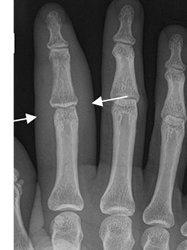

Fig 10. Celulitis.

Rx AP. Prominencia de los tejidos blandos en el 2º dedo, por celulitis. No hay lesiones óseas asociadas.